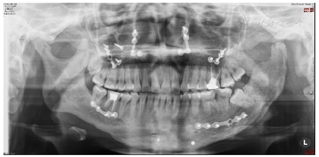

口内检查(图2):

恒牙列,磨牙关系左侧近中,右侧中性,前牙Ⅲ度深覆合,覆盖正常,下颌中线右偏1 mm,左侧前磨牙区开

。

26大面积银汞充填体,46牙色充填体。

32-43对应前庭沟处黏膜可见瘢痕。

曲面体层片检查(图3):左侧髁突膨大,下颌体部及颏部可见钛板钛钉影像。